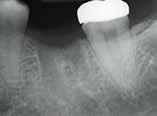

A korai harmicas éveiben járó hölgy rendelőnkbe érkezésének oka a jobb felső nagymetsző fog bizonytalan érzkenysége, elmondása alapján gyermekkorában trauma érte a felső frontrégiót. A frakturált klinikai koronákat kompozittöméssel helyreállították, egyéb kezelést akkor nem tartottak szükségesnek. Az utóbbi hónapokban tapasztalt érzékenység miatt kereste fel rendelőnket. A klinikai vizsgálat (1. és 2. kép) és a CBCT felvétel (3. kép) alapján diagnosztizált külső gyökérreszorpció megoldására a fog eltávolítását, implantátum

bukkális 1. kép: Kiindulási állapot, 2020. január. 3. kép: Kiindulási CBCT felvétel. 2. kép: Kiindulási állapot a palatinális oldal felől.

12. kép: A 6 hónapos intraorális kontrollröntgen felvétele.

A 2020 januárjában elkezdett kezeléssorozat befejezését az év márciusában, hazánkba is begyűrűző Covid-19 pandémia késleltette, így kb. 6 hónap gyógyulás után láttunk hozzá az emergencia profil és a gingivális zenit ideiglenes koronával történő formázásához (11. és 12. kép). A 3 hetente végzett apró alakításokkal sikerült megfelelő ínyprofilt kialakítani, a „rózsaszín esztétika” a páciens számára is megfelelő volt. A bal felső nagymetsző fog meziális kompozit tömés cseréjét követően, individualizált nyitott kanalas lenyomati fejet készítettünk: az akrilát ideiglenes korona profilját átlátszó szilikonnal lemásoltuk, majd a körszimmetrikus gyári lenyomati fej és az ideiglenes korona kontúrja közötti hézagot folyékony kompozittal töltöttük ki (13. kép). Az így készített egyéni lenyomati fejjel vettünk lenyomatot a végleges, kerámialeplezésű cirkónium-dioxid vázas, átmenő csavaros rögzítésű koronához. (A fogtechnikai munkát Nébl Péter fogtechnikusmester készítette.), (14., 15., 16 és 17. képek).